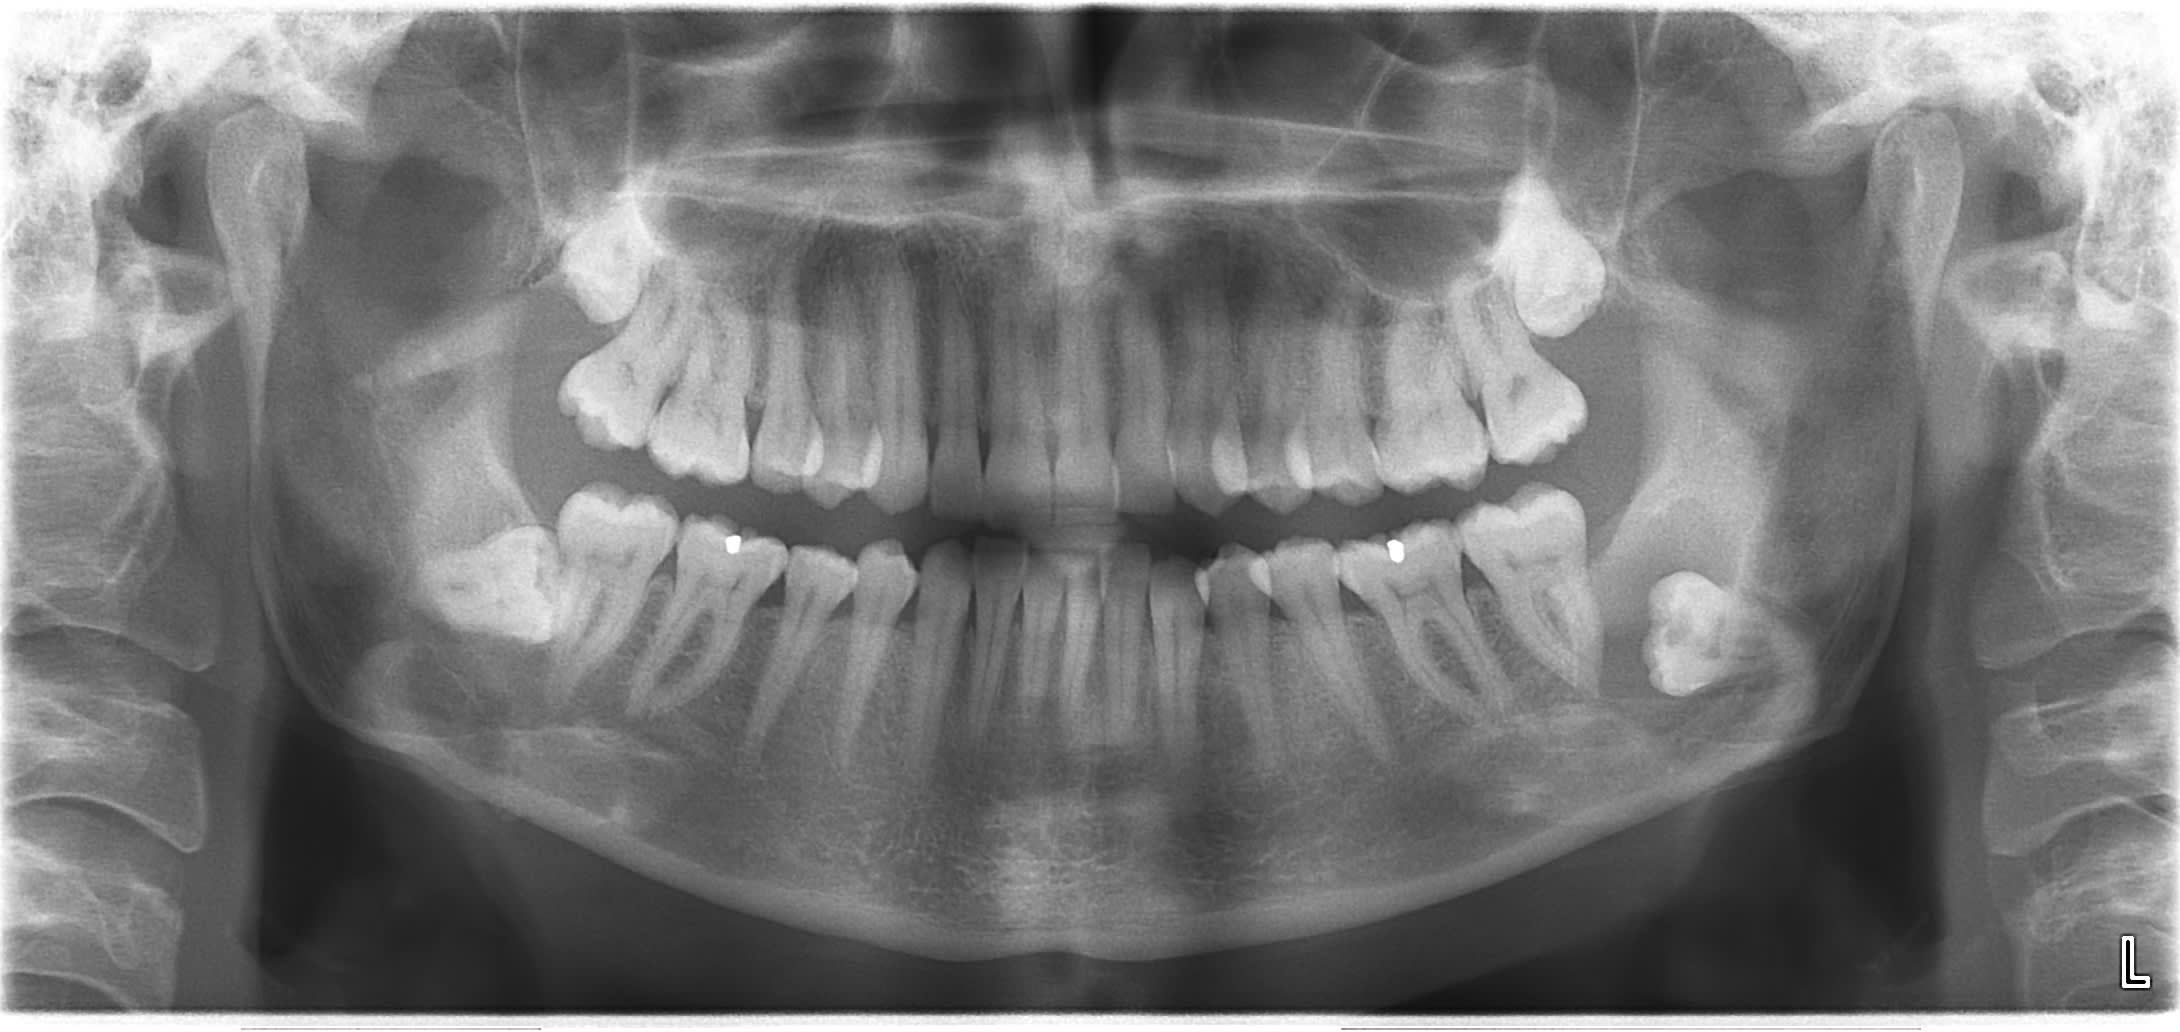

Petit kyste folliculaire. Controle post op 6 semaines. aucune douleur, pas de perte sensibilite labio mentonniere.. :0) ouff

Mr cratère :D

avec la cicat osseuse t'as pas la 7 qui danse ?

Non, son dentiste doit terminer endo fin septembre. pas mobilite aussi surprenant que cela puisse paraitre.